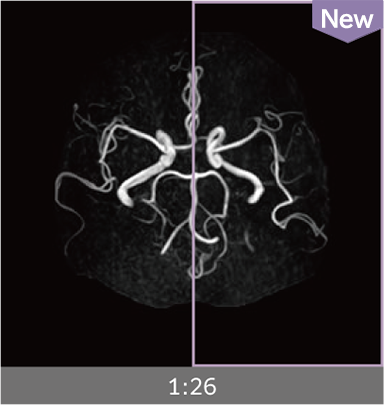

Images can be obtained at high speed by combining two technologies: IP-RAPID, which reduces imaging time while maintaining image quality, and Advanced Reconstruction to improve image quality.

Under-sampling reduces imaging time, and iterative reconstruction with IP-RAPID reduces noise and artifacts.

In addition, Advanced Reconstruction further eliminates noise and produces images that are easier to use in making a diagnosis.